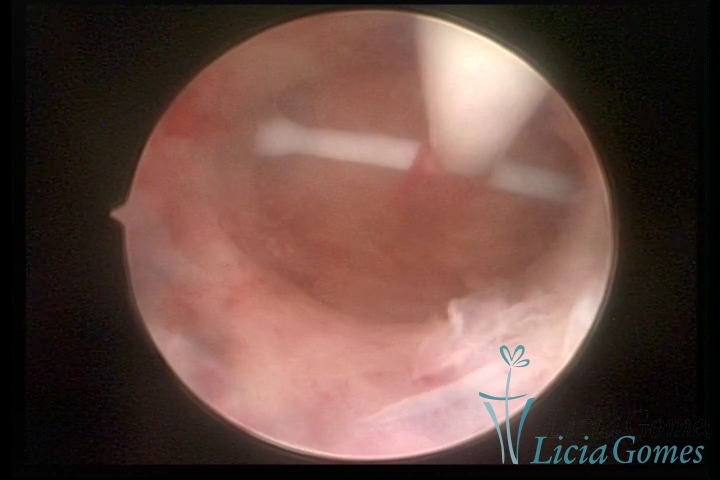

Canal cervical com fio do DIU